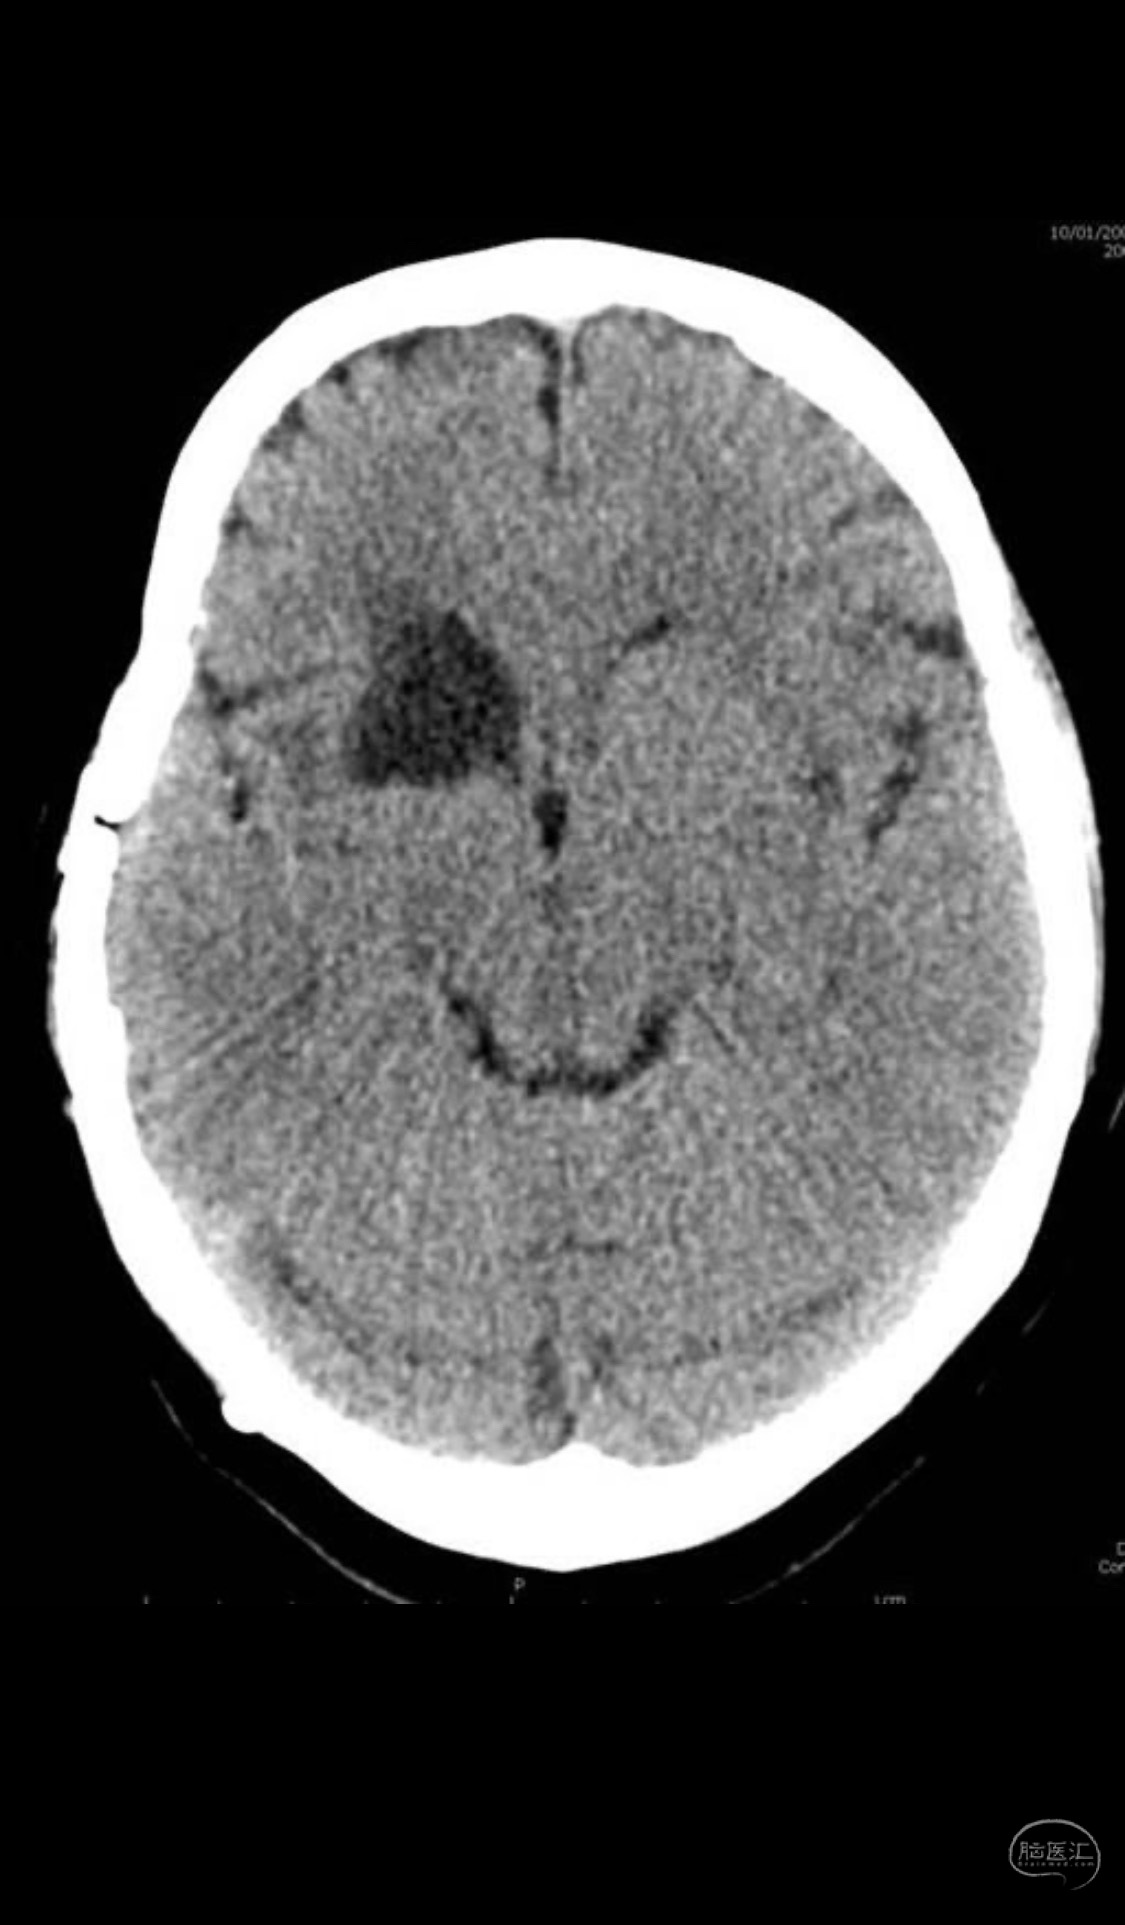

MLS,M79Y,sah,双侧MCA烟雾病,Heubner返动脉瘤,前交通段开窗,细支发出Heubner返动脉,瘤颈细长,瘤颈口比微导管细,弹簧圈2mmx3cm“隔山打牛”填塞治愈,Heubner返动脉保留。

该患者术后2天观察神志清楚,四肢活动正常。